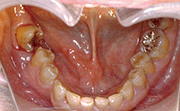

図❶ 初診時、口腔内写真

口腔内所見:7~4相当頬側歯肉に軽度の発赤、腫脹、圧痛を認めた。7は著明に近心傾斜し、6は口腔内には直接みえなかった。7は動揺著明で、歯周ポケットより血性膿の排出がみられた(図❶)。